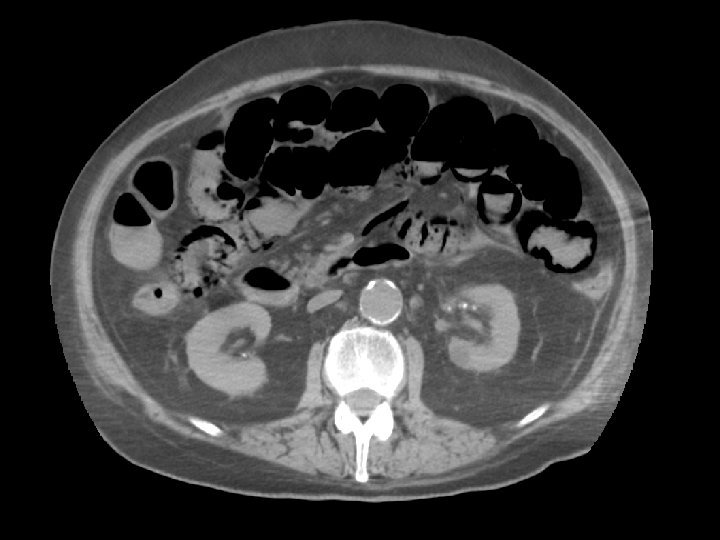

Question 6 • A 64 -year-old man presented to Emergency room because of abdominal pain, vomiting and shortness of breath. The abdomen was distended with no pulsatile mass. His ECG showed atrial fibrillation.

Question 6 • The result of arterial blood gas was as follows: • p. H 7. 029, p. CO 2 1. 93 k. Pa, p. O 2 23. 1 k. Pa, BE – 27, HCO 3 3. 8 mmol/L, Sa. O 2 99% • Na 136 mmol/L, K 4. 0 mmol/L, Cl 95 mmol/L • H’Stix 11. 7 mmol/L • Urgent CT abdomen was performed.

Question 6 (a) Comment on the blood gas and calculate the anion gap. Anion gap metabolic acidosis: Na (+ K) – Cl - HCO 3 = 136 (+ 4) – 95 - 3. 8 = 41. 2 (b) Describe the features of CT abdomen. Pneumatosis intestinalis, porto-venous gas, pneumoperitoneum (c) What is the most likely diagnosis? Ischaemic bowel